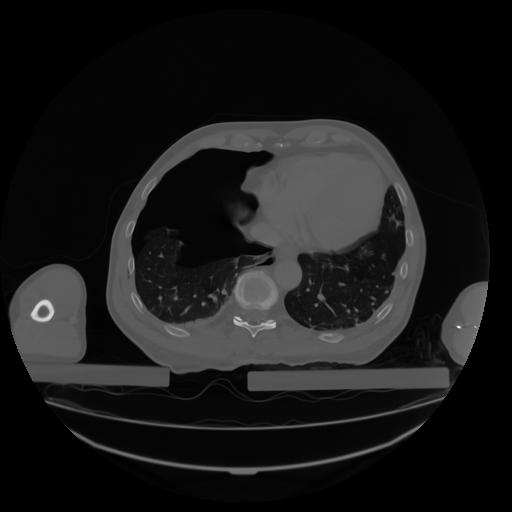

27 CUERPO,CE,Axial,3.0,CUERPO,,